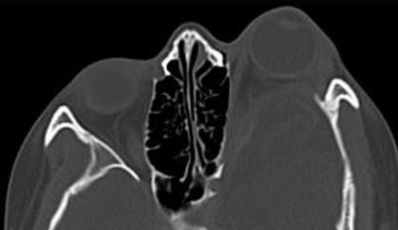

Orbites

- Neurofibromes plexiformes

- Buphtlamie

- Dysplasie de l’aile du sphénoide, asymétrie faciale